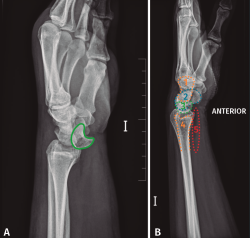

Desde el Servicio de Urgencias se solicita un radiografía anteroposterior y oblicua de mano, muñeca y tercio distal del antebrazo izquierdo. Si observamos detenidamente la radiografía anteroposterior, se observa una alteración en los arcos de Gilula y una posición alterada del semilunar (flexión palmar). Debido a que estas radiografías no son las más adecuadas para el estudio de la muñeca, podría pasar desapercibida la lesión (Figura 1).

Figura 1. Radiografía (A) anteroposterior y (B) radiografía oblicua de mano, muñeca y tercio distal del antebrazo realizadas durante la atención en urgencias inicial. Se observa la fractura de la estiloides radial (flecha). Alteración en los arcos de Gilula (línea). Alteración en la forma del semilunar, en flexión volar (rojo).

El diagnóstico inicial fue de una fractura de estiloides radial no conminuta y no desplazada, decidiéndose tratamiento ortopédico con férula antebraquial palmar. A las 3 semanas, ante la persistencia de tumefacción, dolor e impotencia funcional en la muñeca, se realizó una TC en la que se observó una luxación transestiloperilunar, por lo que se decidió trasladar al centro de referencia, para su valoración y tratamiento definitivo.